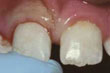

Haljennut tai murtunut hammas - Haljennut tai murtunut hammas tulisi hoitaa välittömästi vakavempien vaurioiden välttämiseksi.

![]() | Haljennut etuhammas |